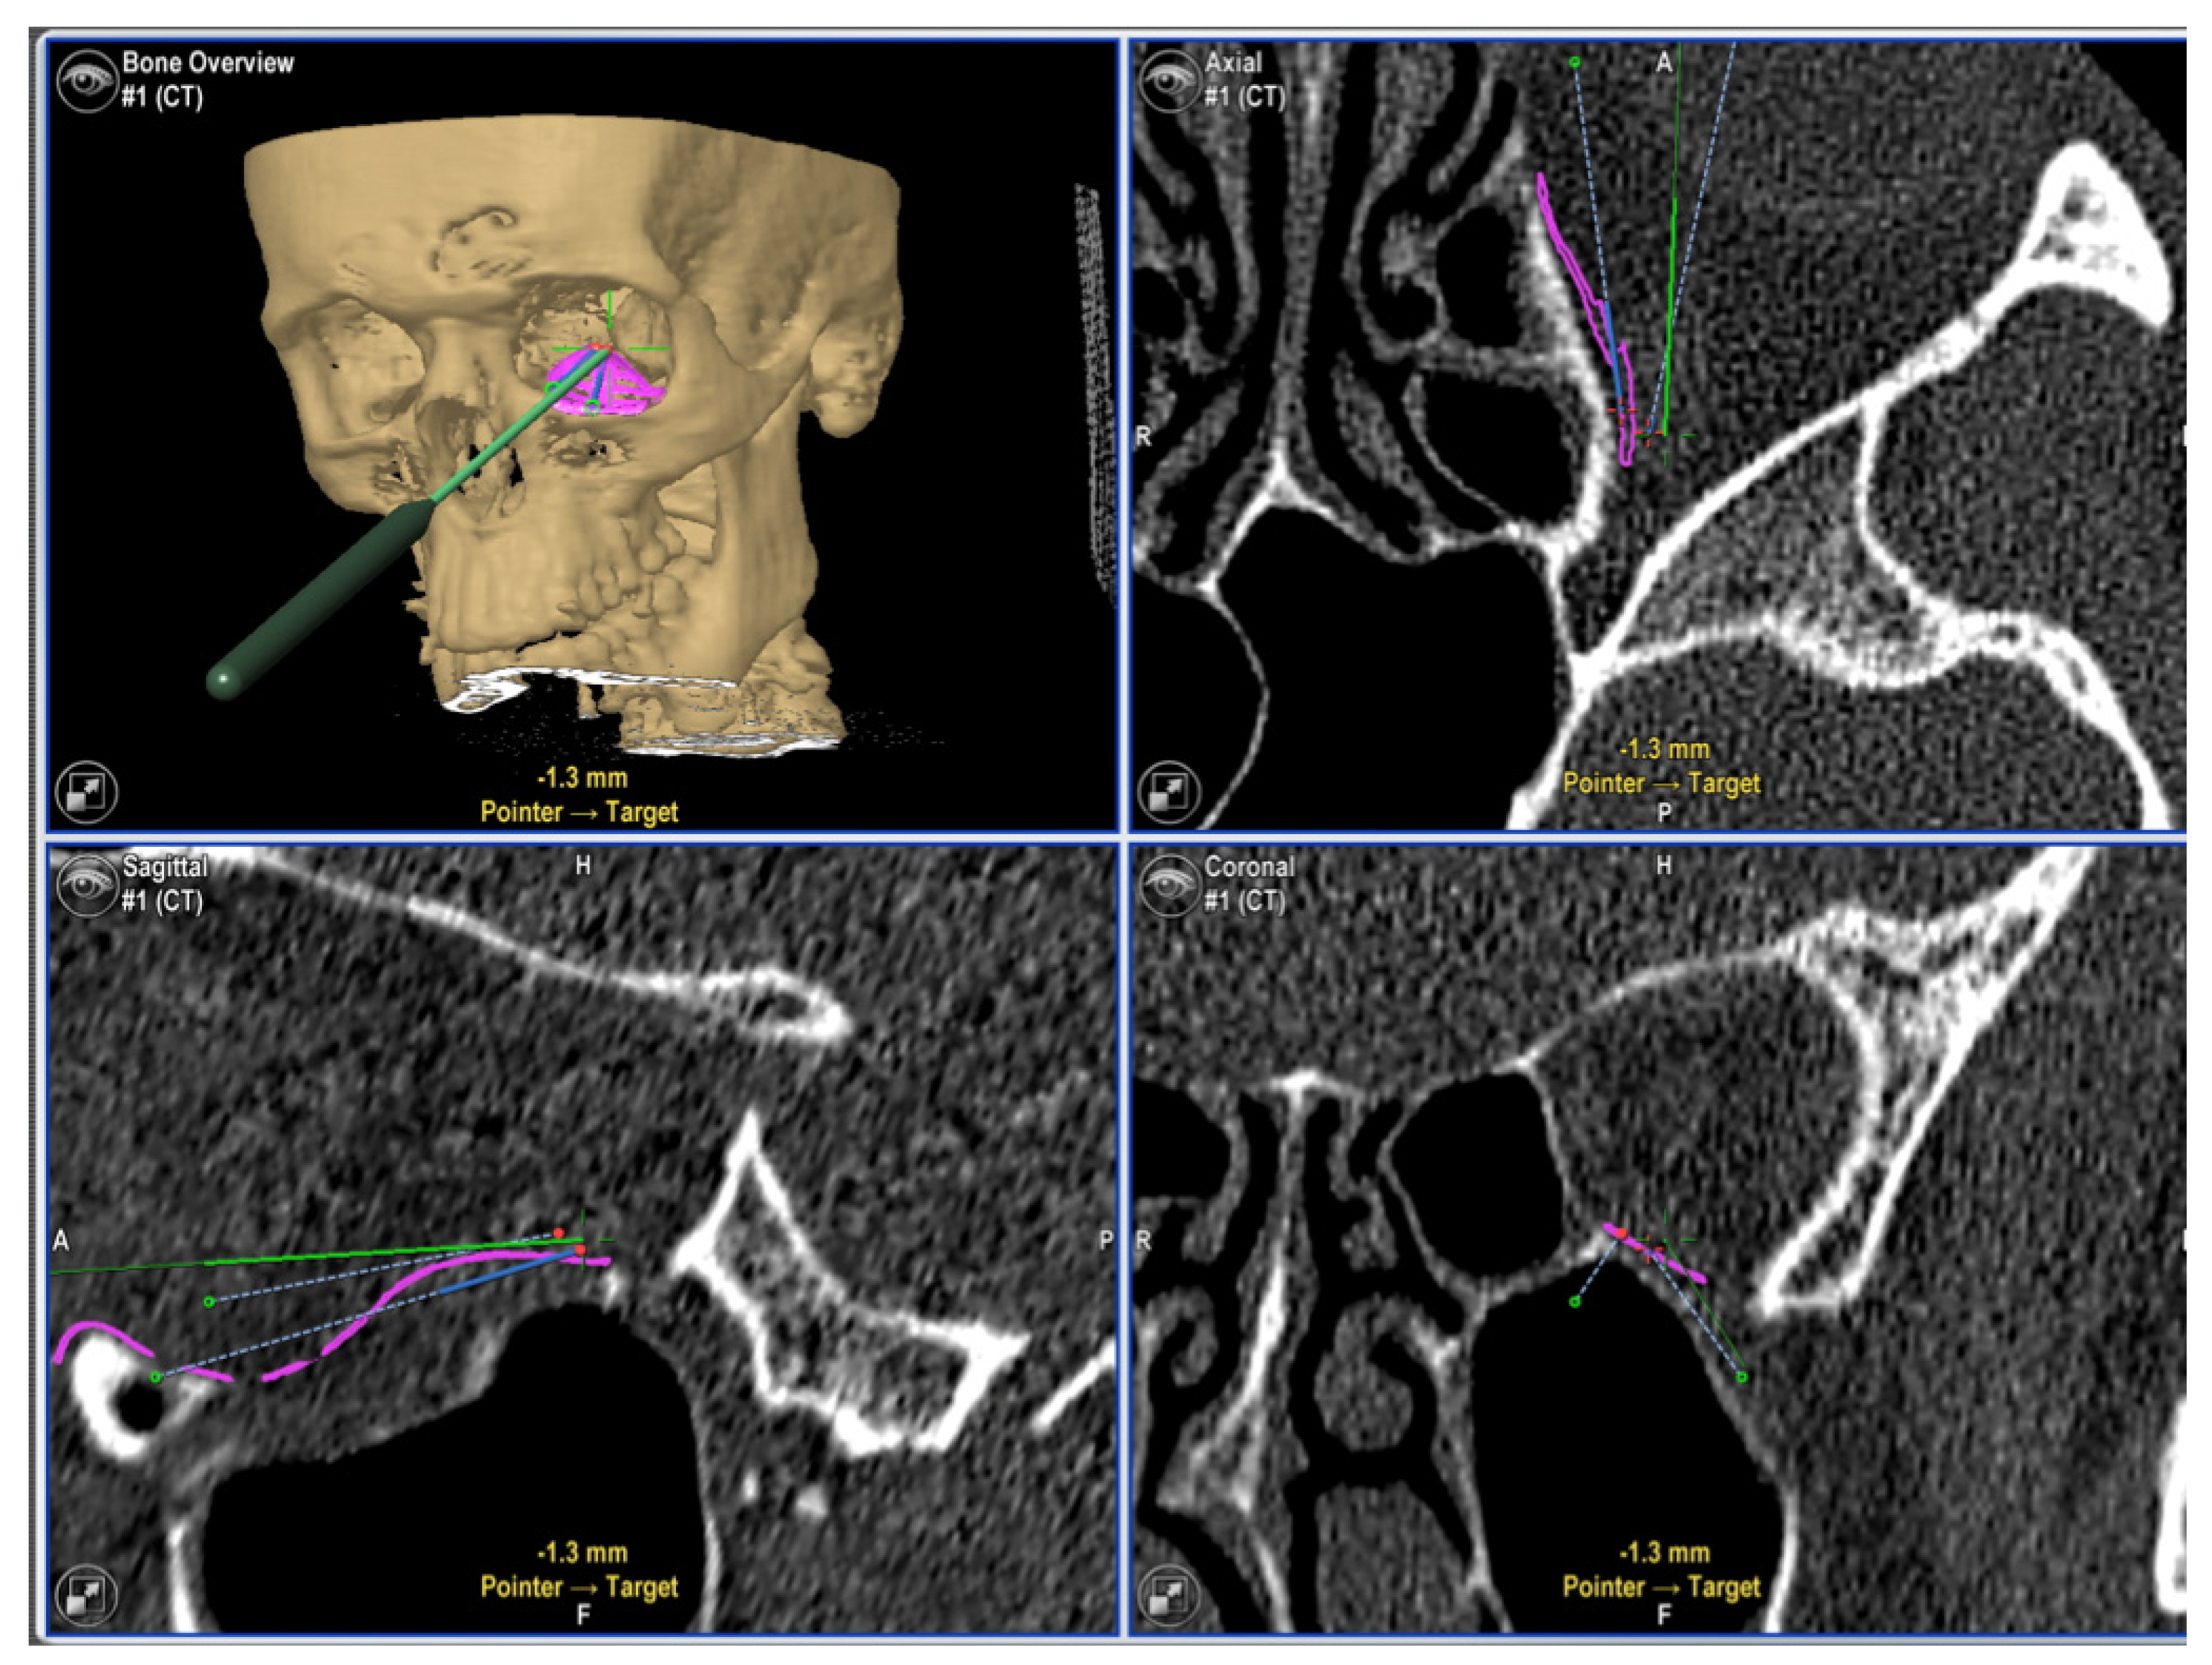

- Rana, M.; Chui, C.H.K.; Wagner, M.; Zimmerer, R.; Rana, M.; Gellrich, N.-C. Increasing the accuracy of orbital reconstruction with selective laser-melted patient-specific implants combined with intraoperative navigation. J. Oral Maxillofac. Surg. Off. J. Am. Assoc. Oral Maxillofac. Surg. 2015, 73, 1113–1118. [Google Scholar] [CrossRef] [Green Version]

- Schramm, A.; Suarez-Cunqueiro, M.M.; Barth, E.L.; Essig, H.; Bormann, K.-H.; Kokemueller, H.; Rücker, M.; Gellrich, N.-C. Computer-assisted navigation in craniomaxillofacial tumors. J. Craniofac. Surg. 2008, 19, 1067–1074. [Google Scholar] [CrossRef]